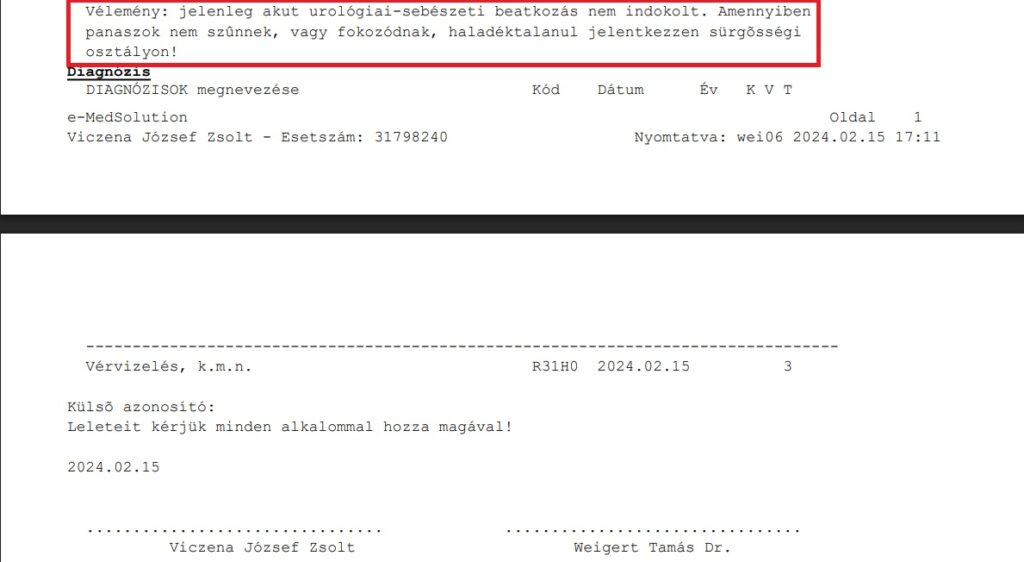

Úgy döntöttünk, hogy felutazunk az ellátás reményében a bp-i Urológiai Klinikára. 5 óra várakozás után Dr Weigert Tamás rezidens/ügyeletes vizsgálta. Elfordította a fejét, amikor a fiam a cola színű vizeletek fényképét meg akarta mutatni – és azért mutatta, mert már úgy érezte, hogy neki kell bizonygatnia, hogy mekkora baj van. A leleteket nem, a tüneteket viszont ő legalább leírta. Saját véleménye viszont nem volt. Azt írta, hogy: „Amennyiben panaszok nem szűnnek, vagy fokozódnak, haladéktalanul jelentkezzen sürgősségi osztályon!” – Ezzel az a baj, hogy az első mondata ugyanakkor ez volt: „Elmondása szerint sürgősségi osztály látta” – ezzel kezdte a fiam, hogy onnan jött ide. És akkor ezt nyújtja egy Urológiai klinika?!!

Dr. Nagy Lajos megnézte a leleteket, majd azt mondta: „Biztosan a gerince fáj… Szerintem a gerince fáj ott, ahol mutatja.” – mire a fiam megszólalt, hogy „A gerincem? Ezek a véseim, a veséim fájnak, súlyos vérvizelés van mellé”. Az orvos ezután nem írta le a 1000-szeres vérvizelés értékeket. A fiam a második (21-ei) alkalommal rékérdezett, hogy miért nem írta le a súlyos leleteket? Képzeljék el, Dr. Nagy Lajos azt mondta, hogy „Azért, mert nincs jelentőségük!” Hihetetlen volt! Ezerszeres vérvizelés értékeknek és Cola-színű vizeletnek nincs jelentősége extrém vesefájdalom társtüneteiként. Ezután kiválasztotta a 2 súlyos lelet mellett készült 3. leletet, ami épp nem tartalmazott vért, lekukocita észterázt, fehérjét, „csak” magas 130 kristályt/látótér és így kiállíthatott egy olyan leletet, hogy Zsoltnak se vérvizelése, se leukocyturiája nincs, így nincs akut, azonnali beavatkozást igénylő állapota se! – Az okot ráfogta a kristályürítésre, és Zsolt ezzel lett magára hagyva ismét.